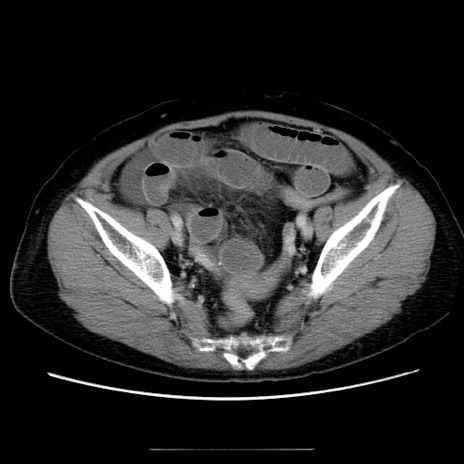

冠状断像

【症例】70歳代女性

【主訴】お腹が張る

【現病歴】1週間くらい前から腹部膨満の自覚あり。昨日夜から増悪したため、本日救急外来受診。

【身体所見】意識清明、BT 36.5℃、BP 165/106mmHg、HR 80bpm、SpO2 98%、腹部:膨満、軟、自発痛・圧痛なし、触診にて不快感あり、腸蠕動音:減弱

【データ】WBC 12600、CRP 1.04